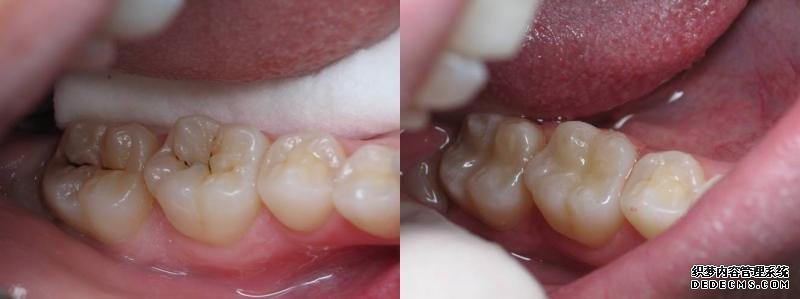

有虫牙怎么办?

有虫牙怎么办?虫牙,又称“蛀牙”、“龋齿”,并不是牙齿中长了虫子,而是口腔中糖和酸共同作用,产生了致龋菌,腐蚀了牙体。虫牙是许多朋友都可能遇到的问题,根据第三次全国口腔健康流行病学调查结果显示,我国5岁儿童、35-44岁中青年、65-74岁老年人的龋齿率均超过了66%,65-74岁老年人更是高达98.4%。目前,临床上治疗虫牙最有效的方法就是补牙,同时越早治疗虫牙,效果越好。

一旦恒牙长了虫牙,就更应及时补牙了,这是因为恒牙一旦脱落了是无法再生的,另外,虫牙是一种破坏性的进行性疾病,不通过补牙是无法治愈的,而且虫牙不及时治疗,拖的时间越久,补牙难度越大。当虫牙导致牙体严重酸蚀缺损后,会直接侵袭牙髓或根尖周,导致剧烈牙疼,夜晚更甚,且伴有阵发性加剧的症状,这时有可能需要先进行根管治疗,清空髓腔和根管内的坏死物质再进行补牙填充,这样不仅增加了治疗难度、治疗费用,而且治疗时间也会延长。根管治疗通常需要2-4次才能完成。